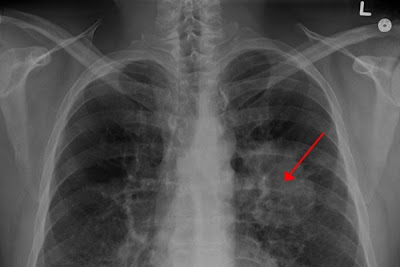

Το Ceritinib είναι ένας από του στόματος χορηγούμενος, εκλεκτικός αναστολέας της κινάσης αναπλαστικού λεμφώματος (ALK), ενός γονιδίου που μπορεί να συντηχθεί με άλλα ώστε να σχηματίσει μια μη φυσιολογική «πρωτεΐνη σύντηξης», η οποία προάγει την ανάπτυξη και την αύξηση ορισμένων όγκων σε καρκίνους όπως ο μη μικροκυτταρικός καρκίνος του πνεύμονα (ΜΜΚΠ).

Η Novartis ανακοίνωσε ότι η Επιτροπή Φαρμακευτικών Προϊόντων για Ανθρώπινη Χρήση (CHMP) του Ευρωπαϊκού Οργανισμού Φαρμάκων (EMA) συνέστησε την έγκριση της επέκτασης της χρήσης του Ceritinib (σεριτινίμπη), ώστε να περιλαμβάνει τη θεραπεία πρώτης γραμμής των ασθενών με προχωρημένο μη μικροκυτταρικό καρκίνο του πνεύμονα (ΜΜΚΠ), οι όγκοι των οποίων είναι θετικοί στην κινάση αναπλαστικού λεμφώματος (ALK+). Εάν λάβει έγκριση, το Ceritinib θα αποτελεί μια νέα θεραπευτική επιλογή για τους ασθενείς που δεν έχουν λάβει προηγούμενη θεραπεία και τους νεοδιαγνωσθέντες ασθενείς με ALK+ προχωρημένο ΜΜΚΠ.

Η θετική γνωμοδότηση της CHMP βασίστηκε στα αποτελέσματα της μελέτης ASCEND-4, μιας τυχαιοποιημένης, ανοικτής επισήμανσης, παγκόσμιας κλίμακας δοκιμής Φάσης III. Η μελέτη έδειξε ότι οι ασθενείς που έλαβαν Ceritinib ως θεραπεία πρώτης γραμμής παρουσίασαν 45% μείωση του κινδύνου εξέλιξης της νόσου σε σύγκριση με τους ασθενείς που έλαβαν την τυπική χημειοθεραπεία της πρώτης γραμμής, πεμετρεξίδης-πλατίνας, με συντήρηση με πεμετρεξίδη (λόγος κινδύνου [HR] = 0,55 [95% CI: 0,42, 0,73]). Η διάμεση επιβίωση χωρίς εξέλιξη της νόσου (PFS) ήταν 16,6 μήνες (95% διάστημα εμπιστοσύνης [CI]: 12,6, 27,2) για τους ασθενείς που έλαβαν Ceritinib, έναντι 8.1 μηνών (95% CI: 5,8, 11,1) για τους ασθενείς στο σκέλος χημειοθεραπείας της μελέτης.